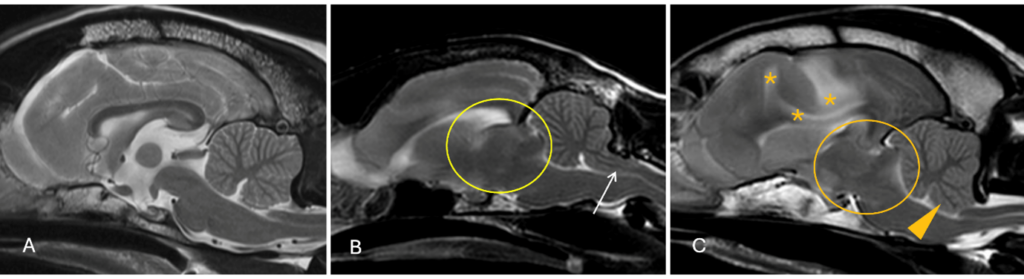

Another contraindication would include suspected or confirmed instability affecting the vertebral column (i.e., atanto-axial instability, or fracture/luxation). Collection of CSF is contraindicated if there is evidence of increased intracranial pressure, that could potentially result in transtentorial or foramen magnum herniation (Figure 1).

In a larger study, 0.15% of dogs experienced a major complication from over 7000 CSF collections performed in a veterinary referral practice setting. Complications included cardiopulmonary arrest or severe neurological deterioration leading to death or euthanasia. Clinical signs that were more commonly picked up in these dogs, included obtundation and multifocal neuroanatomical localisation. Changes that were observed on the MRI studies before the CSF collection, included effacement of the cerebral sulci suggesting expansion of brain parenchyma and dilatation of the ventricular system, suggesting increased intraventricular pressure. Repeat MRI after the complication could aid in understanding in the reason of deterioration (Figure 2).